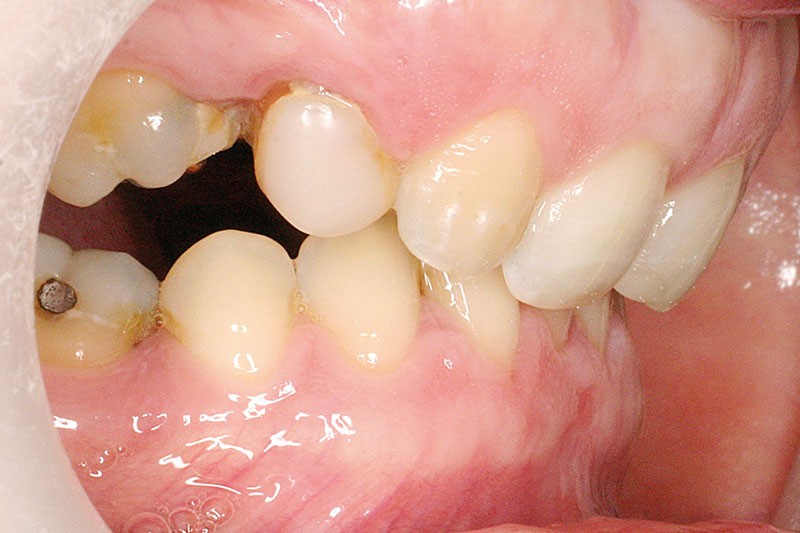

La patiente, âgée de 30 ans, présente des agénésies multiples : 12, 22, 14, 15, 24, 25, 35 et 45 (fig. 1 à 3).